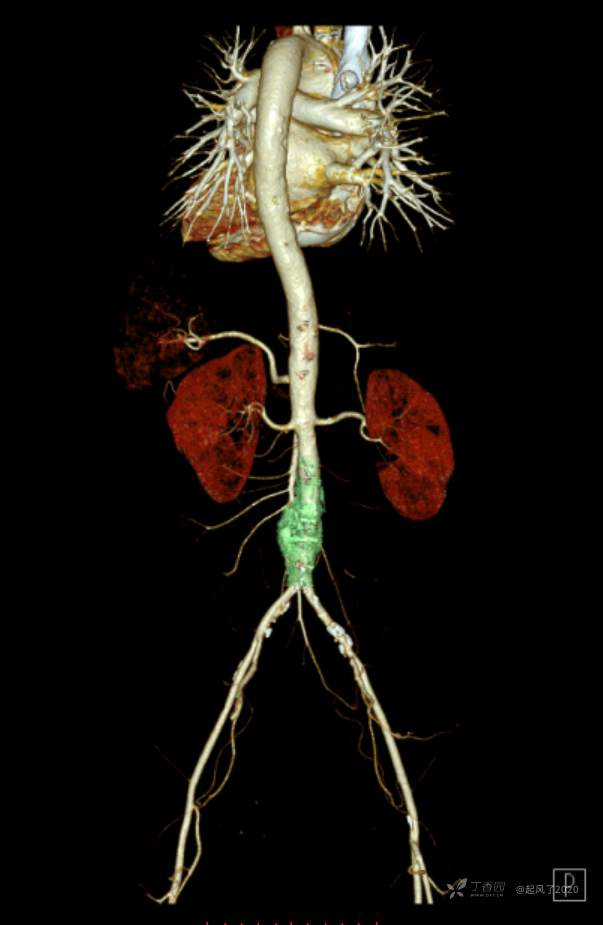

求助 | 女,61岁,下腹部、腰及双髋关节隐痛1月余

II型糖尿病10年余,既往饮食控制血糖在7~8左右,今年1月份开始服用二甲双胍;2009年4月因“子宫肌瘤、双侧输卵管慢性炎症”行子宫及附件切除术;2021年1月体检发现双侧甲状腺多发结节,较大者12*7mm;高血脂10余年,近1月开始规律服药,控制不理想;无高血压